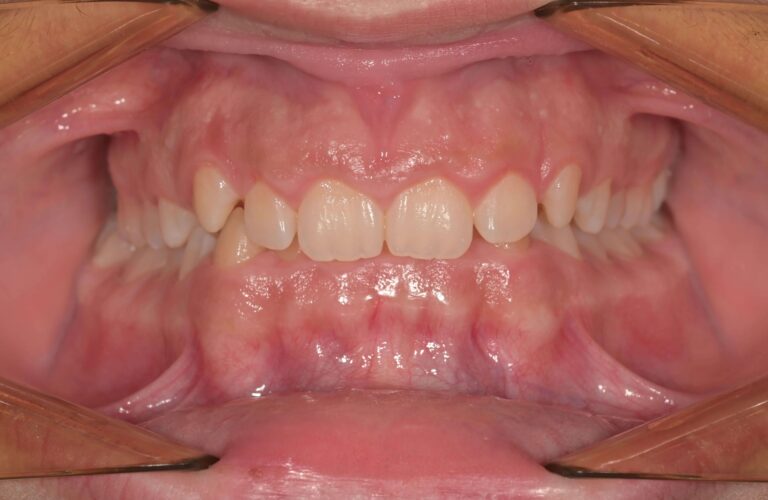

Скупчени зъби

Това е състояние, което се получава, когато няма достатъчно място в устата за всички зъби. Липсата на достатъчно пространство води до припокриване, изкривяване или избутване на зъбите напред или назад. Скупчените зъби често са в резултат на прекалено големи зъби, преждевременна или късна загуба на млечни зъби или недостатъчно пространство в челюстта.

Усложнения, които могат да настъпят – При скупчени зъби добрата орална хигиена е много по-трудна и това увеличава риска от кариес и заболявания на венците. Липсата на лечение води до неравномерно износване на зъбите, което от своя страна води до износване на емайла и чувствителност.